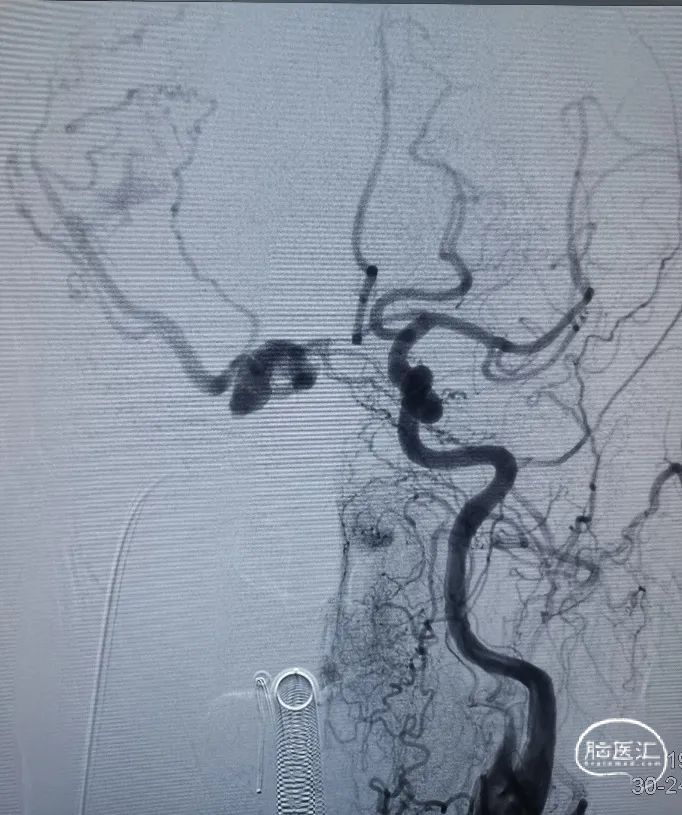

术前造影。

右侧海绵窦硬脑膜动静脉瘘:

· 供血动脉:双侧颈内及颈外动脉分支

· 引流静脉:右蝶顶窦-侧裂静脉-(Trolard静脉-上矢状窦/Labbe静脉-右侧横窦)

· 分型:Barrow D型、Corgnard III型、Borden III型

在Roadmap下,用泥鳅导丝开通右侧岩下窦,泥鳅导丝成功超选至右侧海绵窦内。

造影证实泥鳅导丝位置。

在Roadmap下,用0.014" 微导丝携第1根Echelon-10微导管超选通过开通的岩下窦进入海绵窦内,远端位于瘘口附近,微量造影证实微导管位置。

然后撤出泥鳅导丝,在Roadmap下,用0.014" 微导丝携第2根Echelon-10微导管超选通过开通的岩下窦进入海绵窦内,在3D造影辅助下选取工作角度,将第2根Echelon-10微导管成功超选至右侧蝶顶窦开口处,微量造影证实微导管位置。

调整第2根Echelon-10微导管位置后,先向蝶顶窦开口处填入Jasper®弹簧圈。

然后通过第1根微导管向瘘口处海绵窦注射Onyx栓塞剂。注射过程中通过造影导管在左侧颈外动脉反复造影,直至该海绵窦硬脑膜动静脉瘘完全不显影。最后做双侧颈总动脉造影,见右侧海绵窦硬脑膜动静脉瘘完全不显影,双侧颈内动脉、大脑中动脉、大脑前动脉及其它分支显影良好。行CT示颅内未见明显出血。